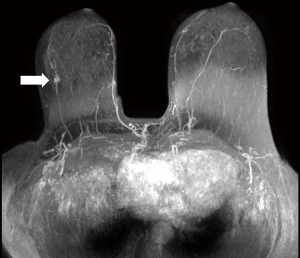

- Screening, an asymptomatic woman of 65 years old, in mammography an architectural distortion is detected in the lateral part of the left breast. The ultrasound findings are subtle with suggested areas of decreased echogenicity. The biopsy under ultrasound guidance reveals DCIS grade 2. The extent of the disease however is not certain. MRI is indicated. MRI shows an extensive process in the lateral part of the left breast resulting in the need of mastectomy (Figure 10).

Figure 10 Mammography of the left breast in cranio-caudal view (A) with architectural distortion (arrow). The distortion is more visible in DBT (B) (arrow). Ultrasound (C) reveals subtle finding of irregular area of decreased echogenicity (arrow). MRI (D) shows extensive area of non-mass-like enhancement in the whole lateral part of the breast (arrow). DBT, digital breast tomosynthesis; MRI, magnetic resonance imaging. - Diagnostic assessment, a patient of 45 years of age with a palpable lump on the right side for 2 months. In mammography with higher proportion of fibroglandular tissue (category C) several areas of increased density with irregular margins and architectural distortions are visible. Ultrasound confirms more than one lesion. MRI demonstrates a large area of enhancement up to 7 cm (Figure 11).